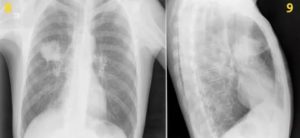

Более высокая результативность наблюдается при создании снимка в двух проекциях: каждый из них покажет тени легких в разных ракурсах, то есть позволит увидеть патологические очаги, которые не были видны с другой позиции.

Выглядит рак на рентгеновском снимке как затемненное пятно. Внешний вид злокачественных опухолей может быть различным в зависимости от формы заболевания, стадии ее развития и других факторов. Составляя описание, врач обращает внимание на локализацию теней. По этому признаку заболевание определяется как центральный или периферический, перибронхиальный или бронхоальвеолярный тип.

Признаками центрального рака легких на рентгене служат очаговые единичные (в редких случаях многочисленные) затемнения — зоны инфильтрации, вблизи которых присутствует ткань с признаками компенсаторной вентиляционной функции. Это проявляется в виде более светлого по окрасу ореола, окружающего тень.

Локализация центрального рака в толще органа, обычно в верхних или средних сегментах. Форма опухоли на снимке определяется как негомогенная лучистая: края новообразования неравномерно «расползаются» в стороны. Также рентген выявляет дополнительную тень в области корней, по форме напоминающую сосудистый рисунок.

По локализации периферический рак легкого значительно отличается от центрального. Очаг поражения тканей располагается на поверхности органа, поэтому проявляется четче. Внешний вид такого типа рака легкого на рентгене стандартный — темная тень с признаками распада тканей.